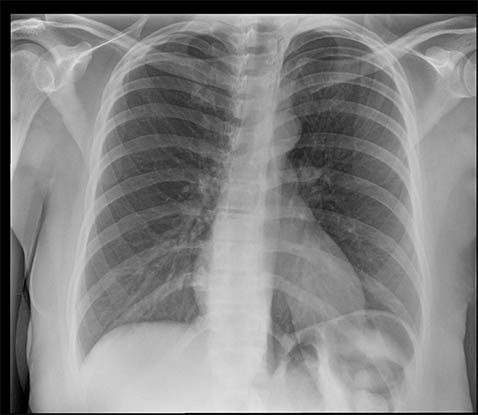

SmartGrid 处理的影像质量与使用防散射滤线栅采集的影像相当,但床边胸部影像方面患者剂量会减少。它会抑制散射的作用,从而改善解剖结构对比度。在不使用防散射滤线栅的情况下,滤线栅状影像质量的好处是加快工作流程并方便放射科技师成像。